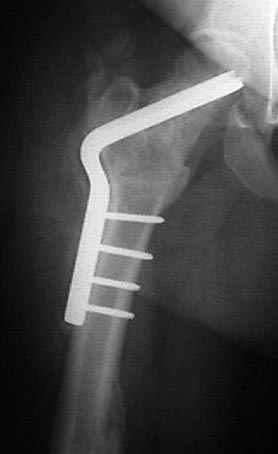

Несколько снимков из моей коллекции, чтобы разьяснить, почему мы до сих пор делаем различные варианты остеотомии.

На рисунке N1 предоперационный план лечения ложного сустава шейки бедра- линия ложного сустава, угол и направление введения импланта, клиновидная остеотомия в градусах и миллиметрах, второй снимок после коррекции, расчет, на сколько удлиняется конечность и размеры импланта;

N3 рисунок окончательный снимок, после операции моя рентгенограмма должен выглядеть примерно как эта картина. На N4 снимке клин перед удалением; N5 послеоперации 3 нед.; N6 окончательная рентгенограмма.

варус при проксимальном отделе 95 градусной пластиной.

Если, например, доводится лечить больных с псевдартрозами шейки бедра, то надобность есть, и приходится. См. приложение.